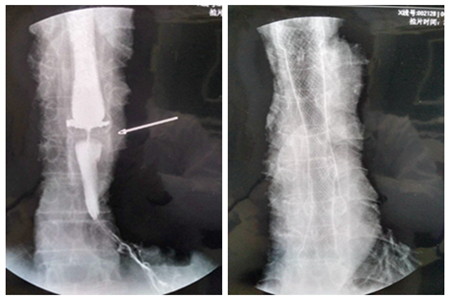

放置支架前、后(狭窄段较长,双支架置入术)对比图